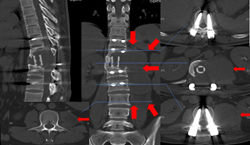

图1-3,术后1年半CT显示肿瘤复发,累及T11-L1椎体,左侧椎旁肿瘤累及腰大肌从T11蔓延到L2-3椎间盘水平。

图1-4,术后1年半MRI显示肿瘤复发,而且再次侵及椎管造成脊髓压迫。